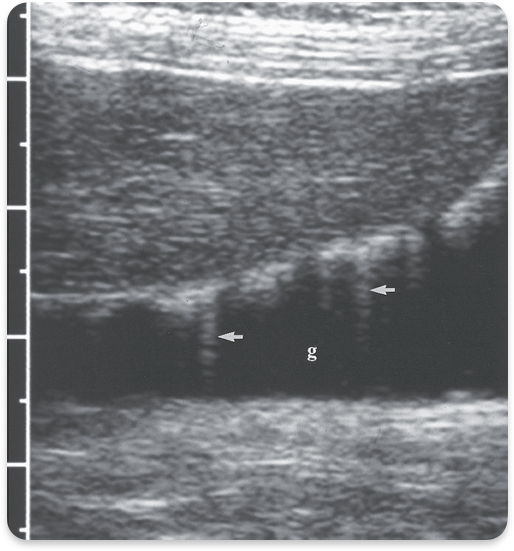

Sludge

Viscid bile, due to biliary stasis

Gallbladder sludge

Sludge with stones